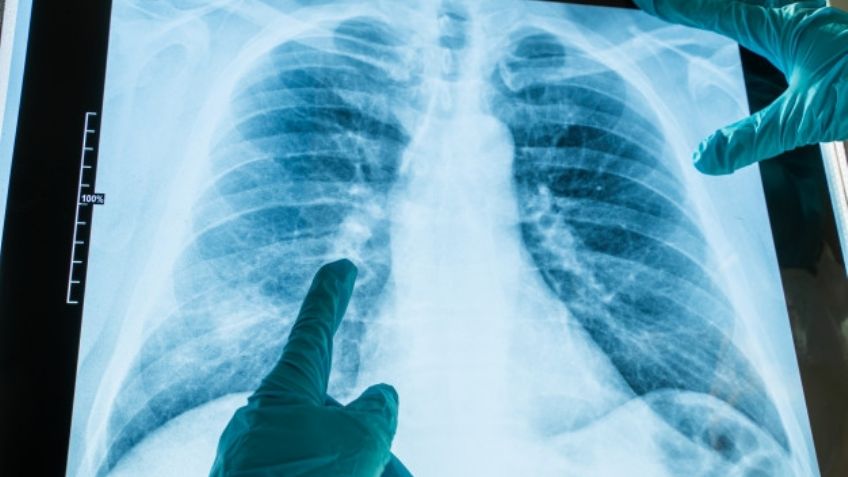

Argentina.- No es ningún secreto que la neumonía puede convertirse en una secuela causada por el Covid-19, sin embargo, recientemente se ha descubierto que el virus puede provocar otra versión de esta enfermedad en los pulmones calificada como bilateral.

A diferencia de la neumonía clásica, este nuevo tipo es mucho más grave y aún no se conoce a ciencia cierta todos los efectos que puede causar en el funcionamiento de los pulmones, pero los expertos creen que podría ser mortal, según sea el desarrollo de la infección por coronavirus.

De acuerdo con expertos del Sanatorio Delta de la ciudad de Rosario, en Argentina, la neumonía bilateral se trata de una especie de taponamiento que detiene la circulación del oxígeno.

Los especialistas aseguran que el 80 por ciento de las hospitalizaciones por SARS-CoV-2 tienen este tipo de complicaciones que se relación directamente con el daño a las células sanas causado por la presencia del virus.

Afortunadamente si es identificada y tratada a tiempo, los pacientes pueden recibir terapias de oxígeno que los ayude a respirar mejor, mientras el resto del cuerpo comienza a ser atendido por los especialistas para disminuir el impacto de la infección.